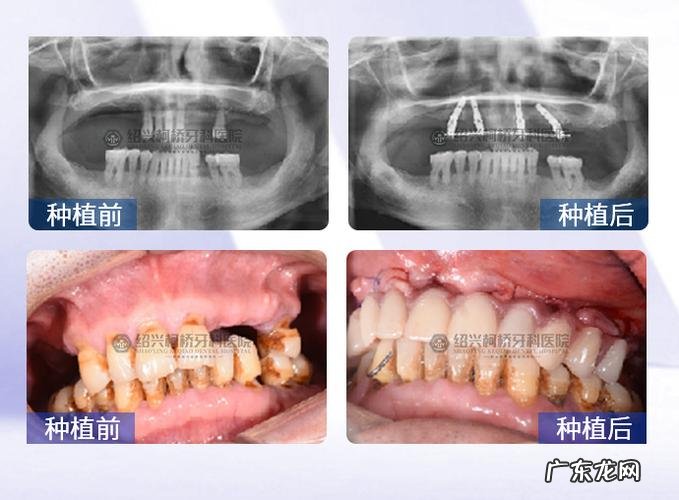

文章插图